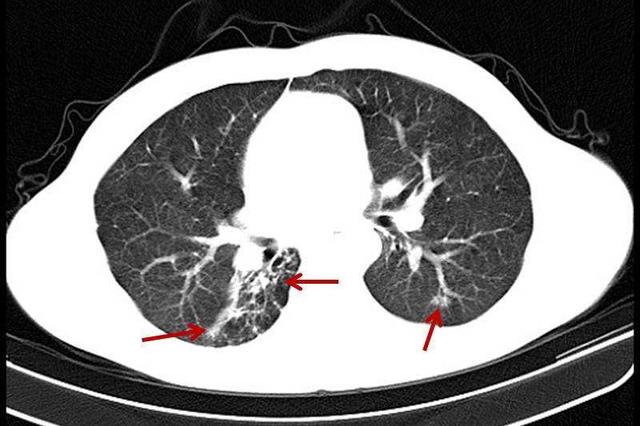

En général, des foyers striés limités ou des foyers calcifiés indiquent qu'il s'agit d'une lésion ancienne, et la figure suivante est une image CT typique d'un patient présentant des foyers calcifiés dans la partie apicale du poumon gauche.

La plus fréquente est l'inflammation ou l'infection des poumons, parce que l'inflammation limitée ou les foyers d'infection dans les poumons dans l'exsudation inflammatoire et l'ensemble du processus anti-inflammatoire, après la stimulation chronique, dans les poumons laissera des foyers locaux de bandes fibreuses, une partie du bord peut tirer la plèvre. Sur le scanner ou la radiographie, cela ressemble à une ligne d'ombres de densité légèrement plus élevée avec des limites claires.

Une autre forme plus courante de tuberculose est la tuberculose pulmonaire ancienne, qui apparaît généralement après la guérison de la tuberculose, sous forme de foyers limités dans les lobes ou segments des poumons où la tuberculose s'est déclarée, souvent accompagnés de foyers ponctuels ou nodulaires de calcification. Il convient d'ajouter qu'en cas de pleurésie tuberculeuse secondaire, de larges foyers de calcification le long de la plèvre peuvent être présents.